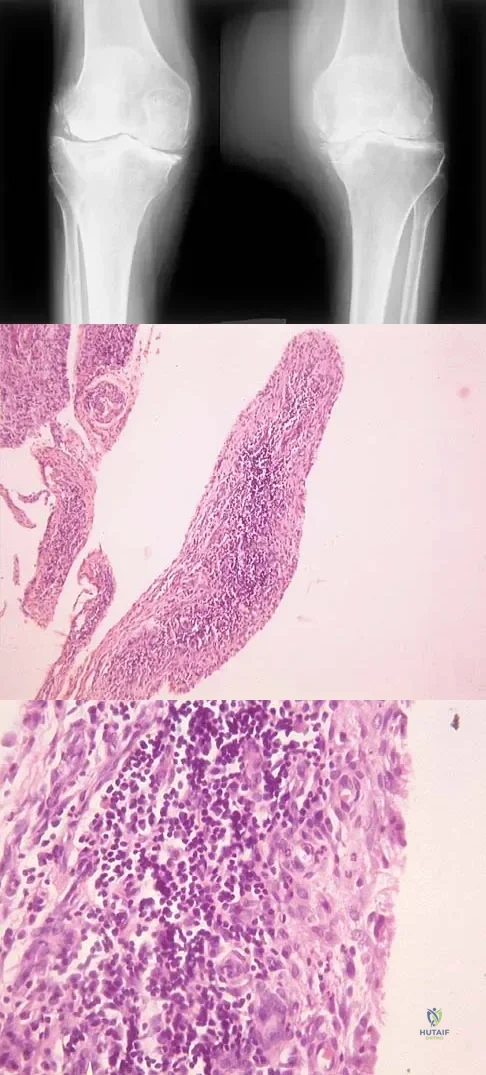

Question 80

A 44-year-old woman has bilateral knee pain, and history reveals bilateral hip replacements. Radiographs are seen in Figure 28a, and histopathologic specimens from the total hip replacement are shown in Figures 28b and 28c. Laboratory studies reveal anemia. What is the most likely diagnosis?

Explanation